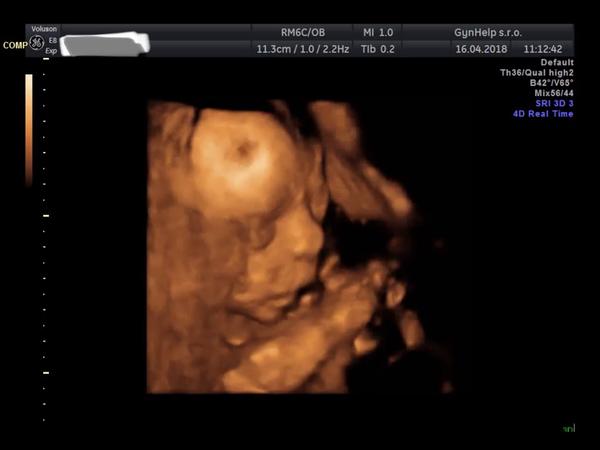

16. dub 2018

Ahoj holky tak jak se vede?